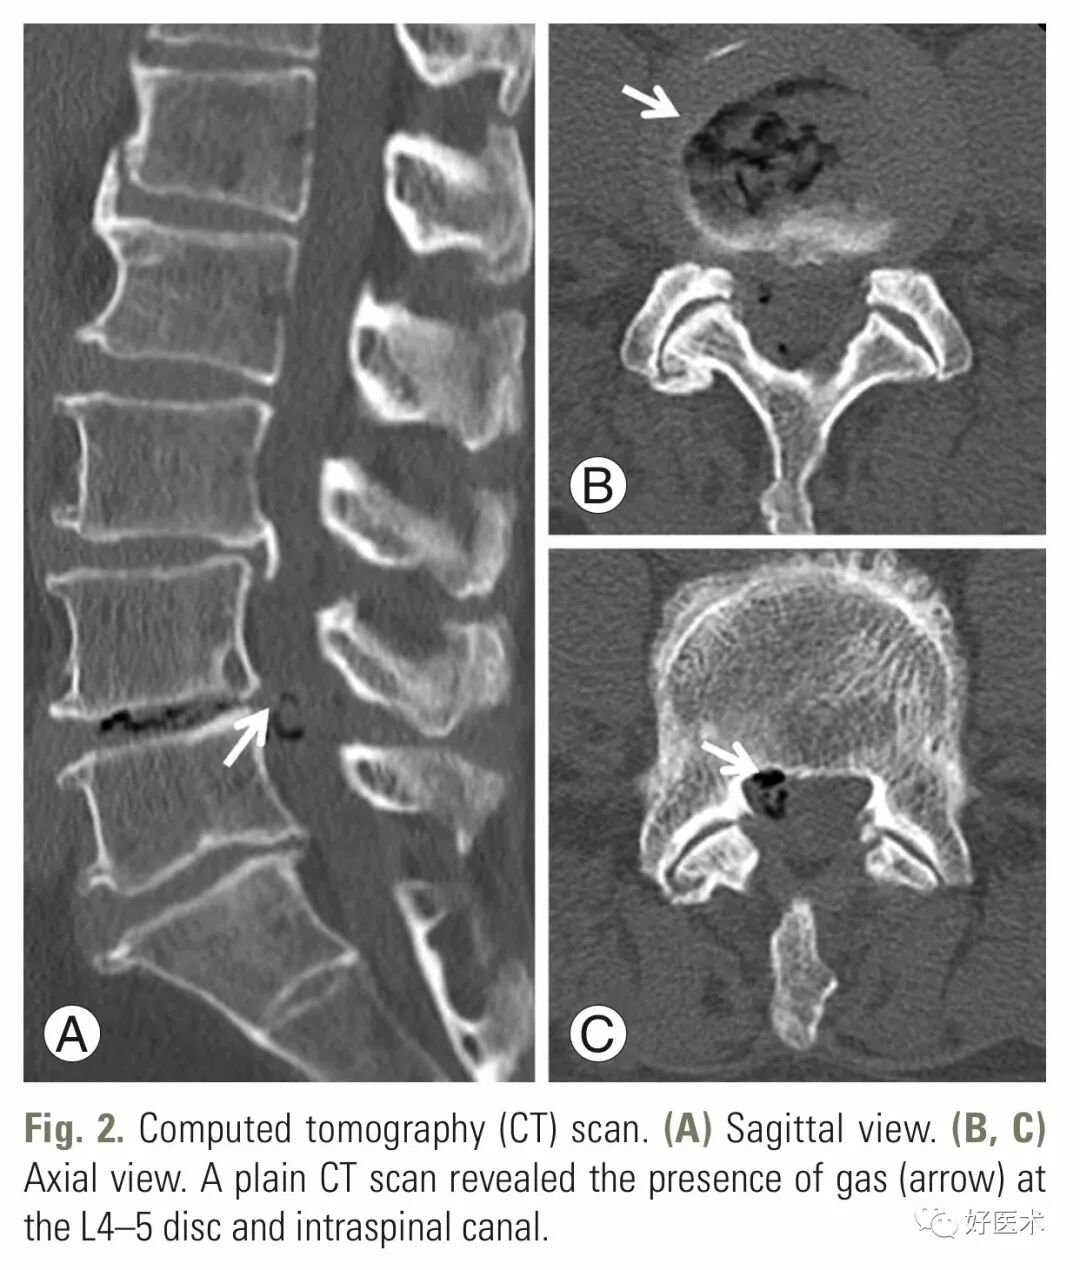

诊断